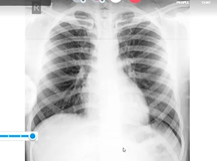

Case Discussion Multivalvular Heart Disease with IE 16th Cardiology Update 2020

Dr Ramakrishnan Clinical Case Discussion Rheumatic Heart Disease 21st July 2020

Dr Sheshagiri Clinical Case Discussion Mitral Stenosis 27th June 2020 incomplete

Clinical Case Discussion Ventricular Septal Defect VSD Dr Sampath Kumar 15th August 2020

Clinical Case Discussion VHD Aortic Regurgitation VSD 16th Cardiology Update 2020